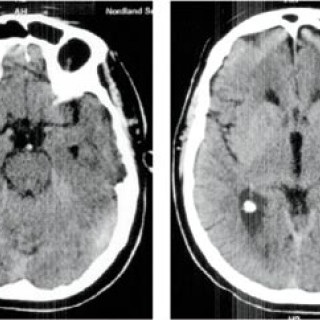

En 52 år gammel etnisk norsk mann ble innlagt i psykiatrisk akuttavdeling etter noen få uker med kraftig økende aktivitetsnivå. Han hadde vist markant endret atferd – blant annet hadde han satt seg fore å sykle åtte mil i kuldegrader og slaps. Ved innleggelsen var han irritabel og snakket fort og nærmest usammenhengende. Somatisk status presens ved innkomst samt orienterende nevrologisk status var normale. Vanlige blodprøver ved innleggelse, inklusive Hb, SR, hvite blodceller, kreatinin, natrium, kalium, ALAT, ASAT, ferritin, folat, kobalamin, FT4, TSH, var alle innenfor referanseområdet...